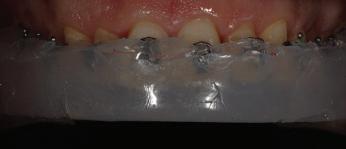

орални снимки и снимки на позата, пал пация на мускулите, брукс-чекър, оклу зограми, кондилография, рентгеногра фии, СВСТ и ядрено-магнитен резонанс на темпоромандибуларните стави). Преди началото на ортодонтското лечение всички стари възстановява ния бяха свалени и бяха заменени с дъл госрочни временни от хибридна керами ка. На девитализираните зъби бе прове дено ендодонтско релечение. Индивиду ализиран оклузален сплинт бе направен с цел да се постигне контролирано репо зициониране на долната челюст, като носенето му продължи три месеца до възстановяване на правилната позиция на ставния диск и затихване на орофаци алната болка и дискомфорт в ставата. Брекетите в горната челюст бяха за лепени, за да започне подреждането и нивелирането на зъбите, докато паци ентът все още носеше сплинта. След края на терапията със сплинта бе на правена кондилография, за да се потвър ди триизмерната позиция на долната челюст. След залепване на брекетите в долна

та челюст 4 минивинта (TADs) бяха по ставени в максилата – 2 в небцето и 2 интрарадикуларно във фронта, с цел да се извърши интрузия на цялата зъбна дъга, да се коригира гингивалната усмивка и да се позволи провеждането на обратна на часовниковата стрелка авторо